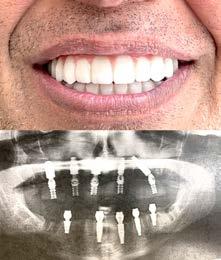

# 22 (2022) • 20 ноября Газета «Диаспора» – все о нас с вами Questrial Open Sans ПО ВОПРОСАМ РАЗМЕЩЕНИЯ РЕКЛАМЫ ОБРАЩАЙТЕСЬ ПО ТЕЛЕФОНУ: (916) 487-9701 или (916) 705-0739 10 8631 BOND RD. Замещение всех зубов на 4-х, 6-ти имплантах Одиночные импланты Несколько имплантов ИМПЛАНТАЦИЯ ЗУБОВ Установка одного импланта от FREE Consultation and CT-Scan Лучшее качество услуг и материалов по разумной цене! Консультация и 3D снимок в подарок. 911 Reserve Dr., Ste #150, Roseville, CA 95678 | Phone: (916) 827-3605 $998* (916) 827-3605 Высококлассные услуги по Зубной Имплантации в современной клинике, лимиторованной на установку имплантов. * - установка 1 (одного) импланта не включая абатмент и коронку. Имплантация будет производится одним из специалистов клиники под руководством доктора Александра Антипова, челюстно-лицевого хирурга. Цена указана для пациентов, оплачивающих наличными. Все-на-5-ти имплантах + несъемные зубы за 1 день Одна из недавних операций: 5 СОВЕТОВ ДЛЯ ЗДОРОВОГО ПРАЗДНИЧНОГО СЕЗОНА Обезопасьте себя от КОВИД-19 во время праздников. Устанавливать правила - это нормально! Неважно, идет ли речь о том, чтобы все были привиты в срок от КОВИД-19 или сделали тесты, все хотят отпраздновать безопасно. Будьте здоровы, чтобы в полной мере насладиться всеми торжествами. Получение вакцины